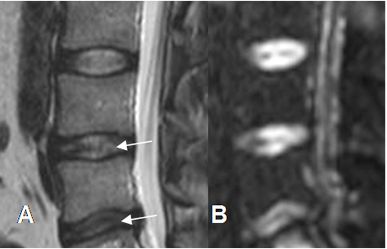

La fisura, ruptura del anulus o lesión HIZ (High Intensity Zone), son disrupciones de las fibras o de su inserción vertebral, que se identifica como un área focal de aumento de la señal en T2. (4,5). (Fig 42).

Fig 42. Ruptura del anulus.

A: RM sagital en T2 y B: RM axial en T2. Hiperintensidad en la parte posterior del anillo fibroso, por fisura o ruptura de sus fibras.